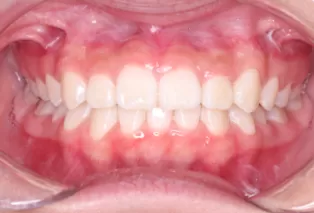

Photos intra-orales